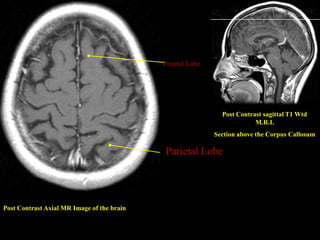

Post Contrast Axial MR Image of the brain

Frontal Lobe

Post Contrast sagittal T1 Wtd

M.R.I.

Section above the Corpus Callosum

Parietal Lobe

Frontal Lobe Post Contrast sagittal T1 Wtd M.R.I. Section above the Corpus Callosum Parietal Lobe Post Contrast Axial MR Image of the brain